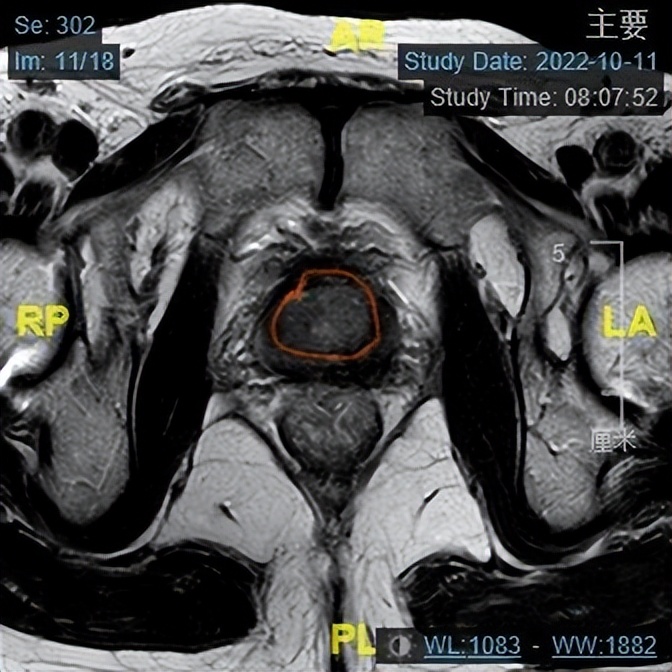

出院后杨大爷定期使用新辅助内分泌治疗,3个月后再次到我院就诊,复查TPSA及前列腺MRI,TPSA降至0.06ng/mL,游离PSA/总PSA为0.32,前列腺MRI提示病变与3个月前比较,病变范围缩小,前列腺大小约18g,与3个月前相比明显缩小。王春阳主任认为杨大爷现在行手术治疗,术后效果能达到预期。

第二次前列腺MRI